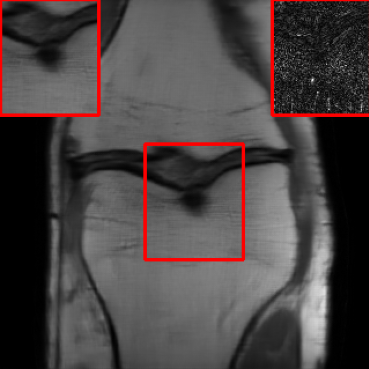

Results for the DIDN-based Reconstructor: To demonstrate adaptability to different network architectures, Table II compares reconstruction performance on the test set with the DIDN denoiser-based MoDL architecture. Average PSNR values with LONDN-MRI are compared to those with networks trained globally at different training set sizes. We ran only iteration of LONDN-MRI, where the reconstruction with a pre-trained (global) network was used to find neighbors. PSNR values for the oracle LONDN-MRI reconstructor are also shown. The overall performances with the DIDN-based architectures are better than with the UNet-based unrolled networks. The PSNRs for LONDN-MRI are consistently and similarly better than for the globally trained network across the different training set sizes considered, indicating potential for LONDN-MRI in improving state-of-the-art models. Fig. 6 visually compares reconstructions and reconstruction errors (in zoomed in region) for different methods. We can see that the LONDN reconstructors capture the original image features more sharply and accurately than the globally learned reconstruction.

| Ground Truth | Global | LONDN-MRI | Oracle |

![]() |

| PSNR = dB | PSNR = 34.15 dB | PSNR = 34.46 dB | PSNR = 34.54 dB |